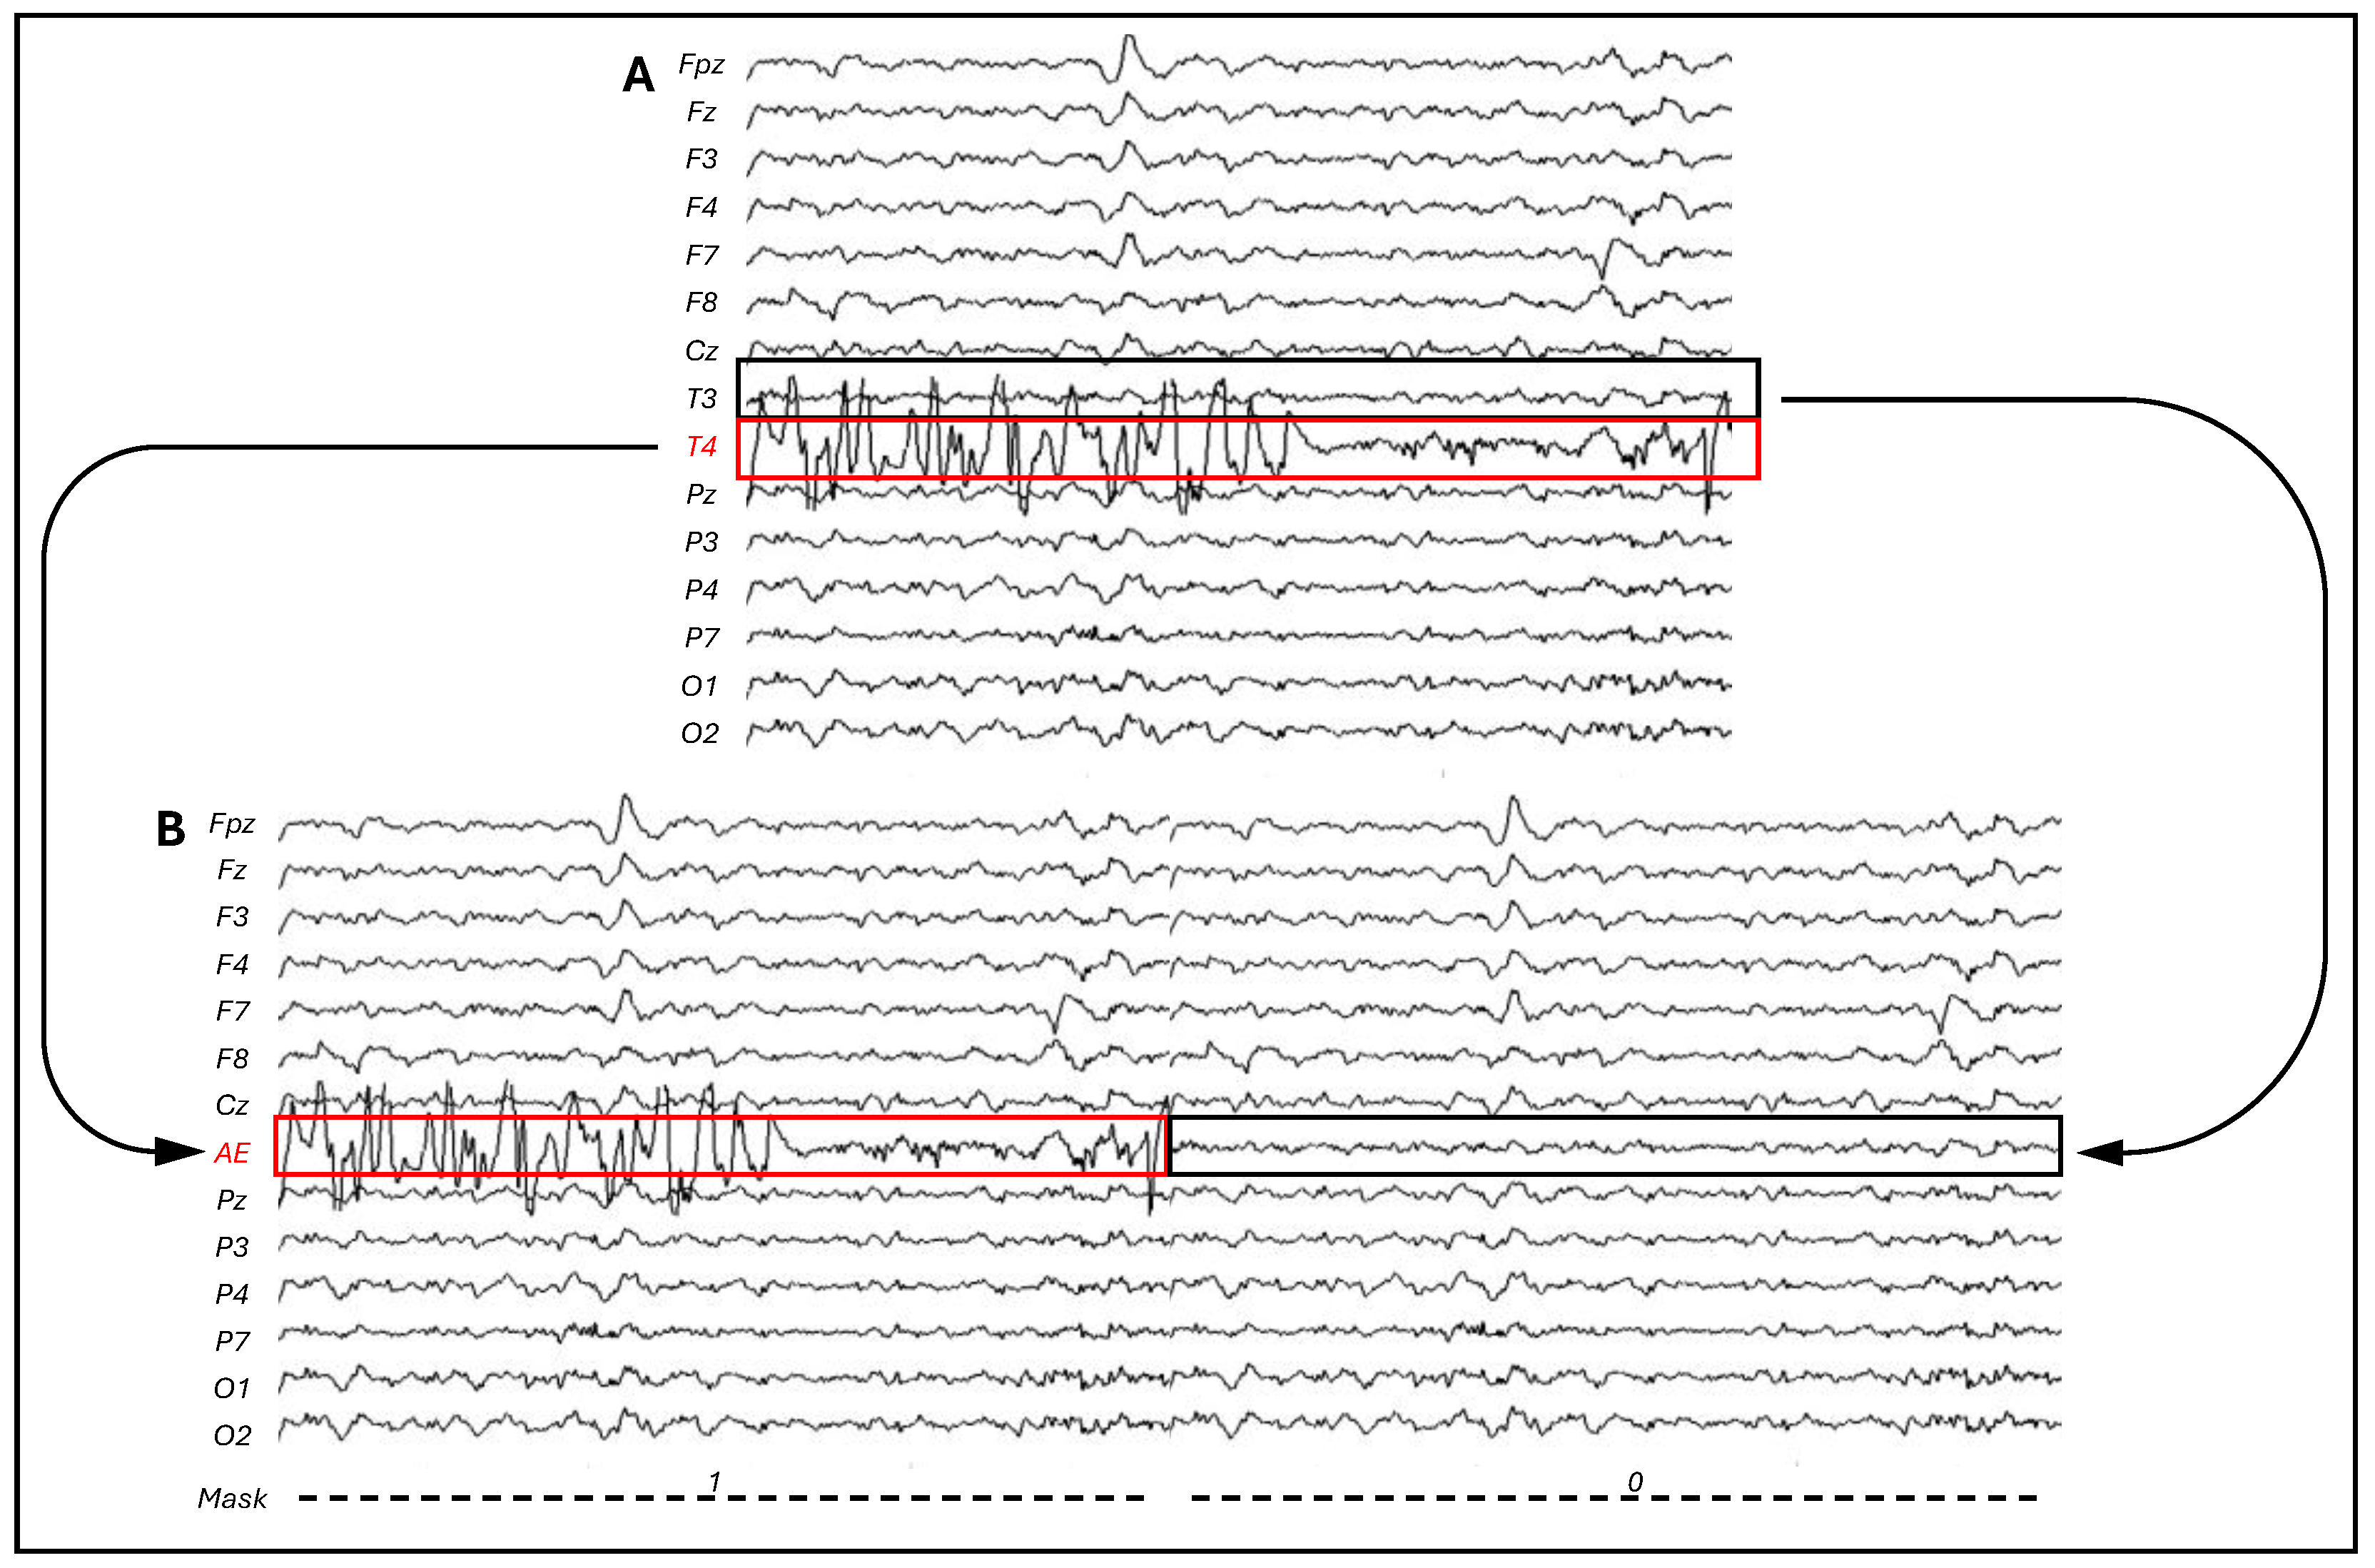

3.1. CI Artifact Characterization

3.2. CI Artifact Reduction